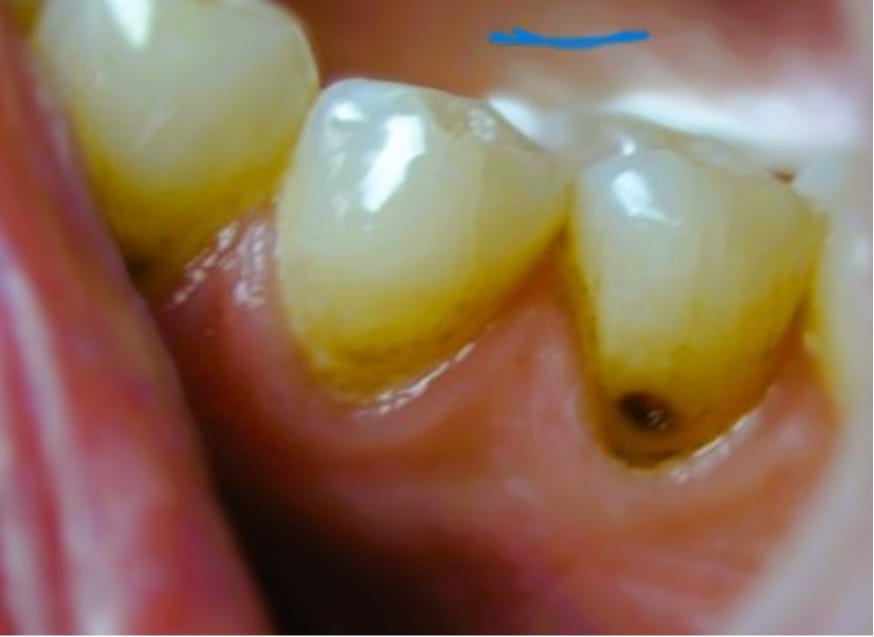

- Följ upp behandlingen inom 2-4 veckor för att bedöma kavitetens aktivitet. Har den inte mörknat och/eller hårdnat vid sondering kan behandlingen återupprepas

Efter applicering blir den behandlade tanden permanent missfärgad, vilket kan upplevas som ett kosmetiskt problem. Enligt en översiktsartikel verkar dock merparten av barn och föräldrar acceptera utseendet [Magno et al. 2019]. Det är trots allt viktigt att patienter, barn och föräldrar tydligt informeras om detta och får möjlighet att väga fördelarna mot nackdelarna. Missfärgningarna kan delvis motverkas genom applikation av kaliumjodid efter SDF men det finns motsägande uppgifter om det påverkar behandlingens effektivitet. Ett annat sätt att undgå visuella missfärgningar är att göra en temporär fyllning i kaviteten efter SDF behandlingen.